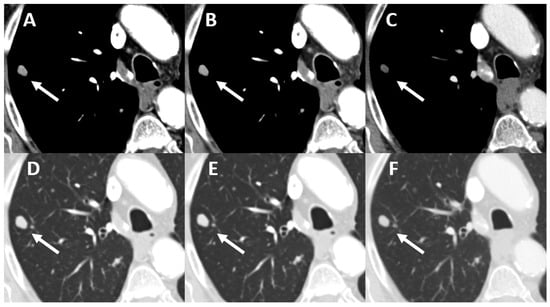

3.4. Subjective Image Quality